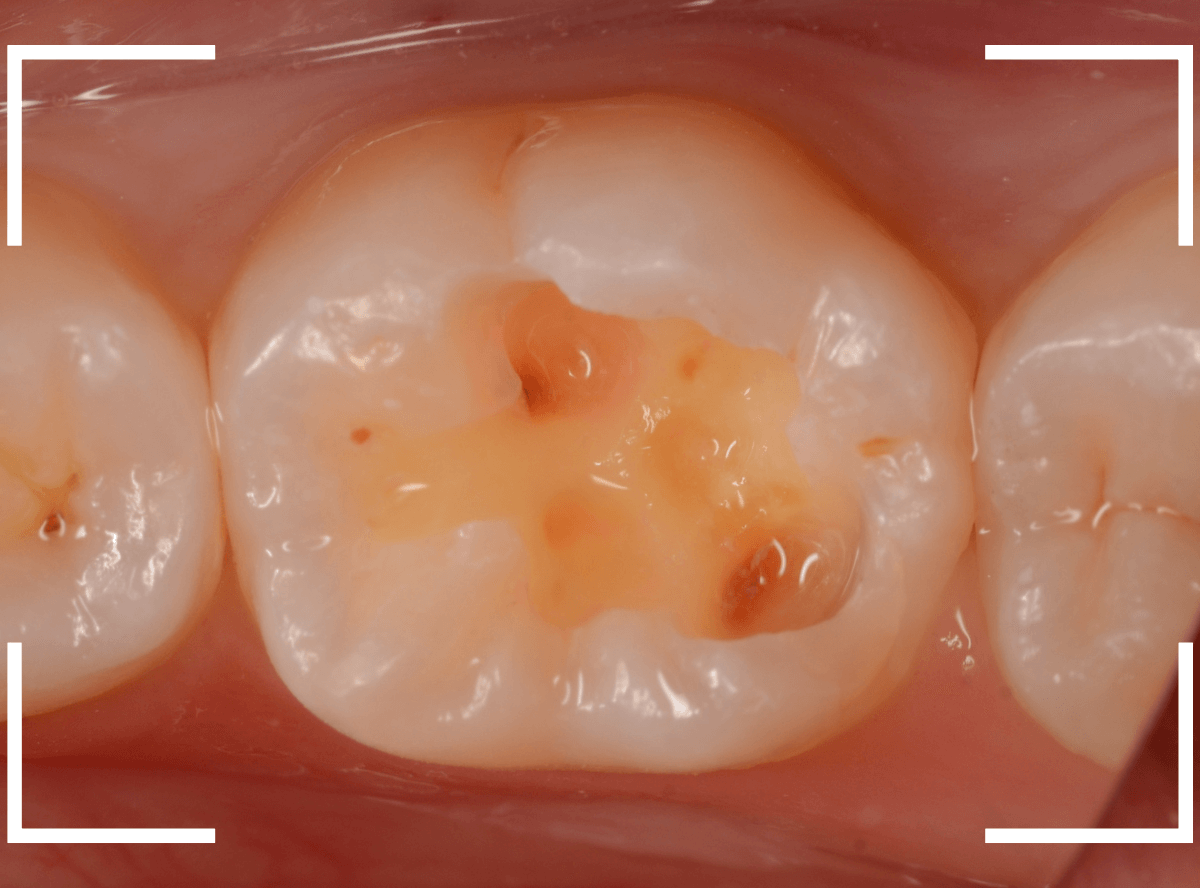

Case.4 レントゲンでわかりづらい、側面の虫歯

検診希望で受診された患者さんです。

歯の溝(裂溝)に虫歯がありそうな歯が見つかりました。

レントゲン写真で確認しますが、虫歯らしき写り方はしていません、浅い虫歯なのでしょうか。

関係ないですが、歯石は確認できますね。

あとは、歯の溝の虫歯を少しずつ除去しながら確認するしかありません。

すると、歯の側面に深めの虫歯が出てきましたので、慎重に虫歯を除去します。

全ての虫歯を除去しました。

今回のように、歯の側面の虫歯は、通常のレントゲン写真でわかりづらく、意外と深い虫歯になっている事があるので要注意ですね。

今回は、通常のレジン治療で終われました。

側面の虫歯を症状が出る前に見つけられたのが幸いでした。